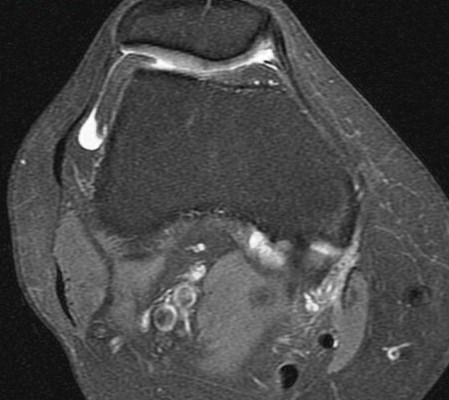

Figure 1 for case Partial tear of the tendon of the medial head of the gastrocnemius muscle ( RID2921 )

Figure 1